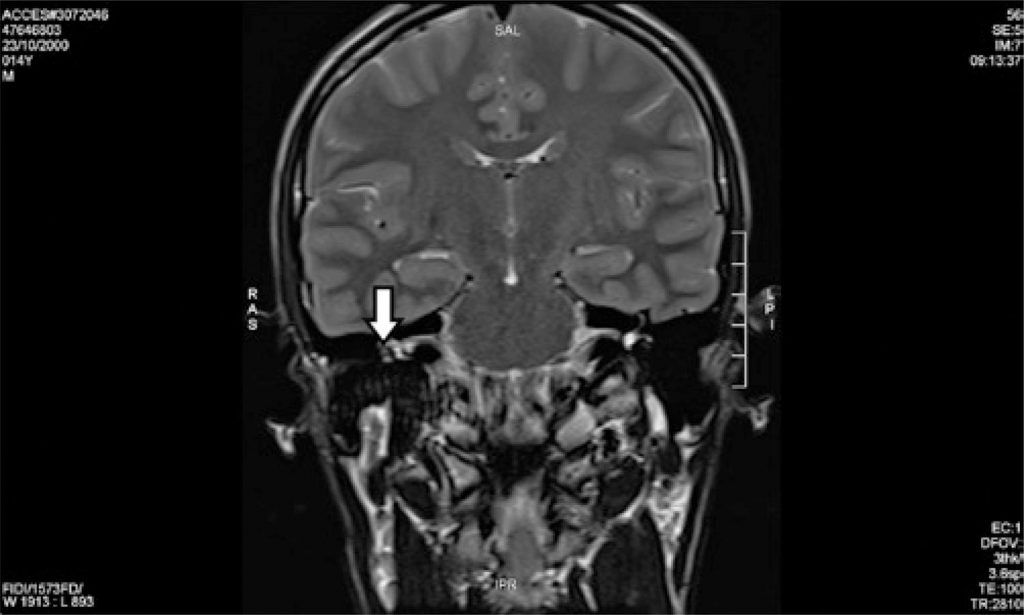

O hemangioma do nervo facial é um tumor vascular raro e benigno, que corresponde a 0,7% dos tumores intratemporais. Apresentamos o segundo caso descrito na literatura de hemangioma do nervo facial em sua porção timpânica. Paciente de 14 anos, sexo masculino, apresentando hipoacusia progressiva em orelha direita com mímica facial preservada. A audiometria evidenciou perda condutiva moderada à direita. A ressonância magnética demonstrou lesão expansiva, comprometendo o segmento timpânico do nervo facial direito, sugestiva de hemangioma do nervo facial. A conduta foi expectante. No primeiro caso descrito na literatura de hemangioma do facial em orelha média, o sintoma que levou o paciente ao atendimento médico foi paralisia facial. No presente caso, pode-se inferir que o primeiro sintoma foi a perda auditiva condutiva ipsilateral à lesão. A paralisia facial pode não estar presente, e o quadro clínico pode se assemelhar à otosclerose, disjunção de cadeia e síndrome da terceira janela, dentre outros diagnósticos diferenciais de perdas auditivas condutivas. O artigo relata o segundo caso de hemangioma do nervo facial em sua porção timpânica, mostrando a peculiaridade de perda auditiva condutiva como única manifestação clínica.